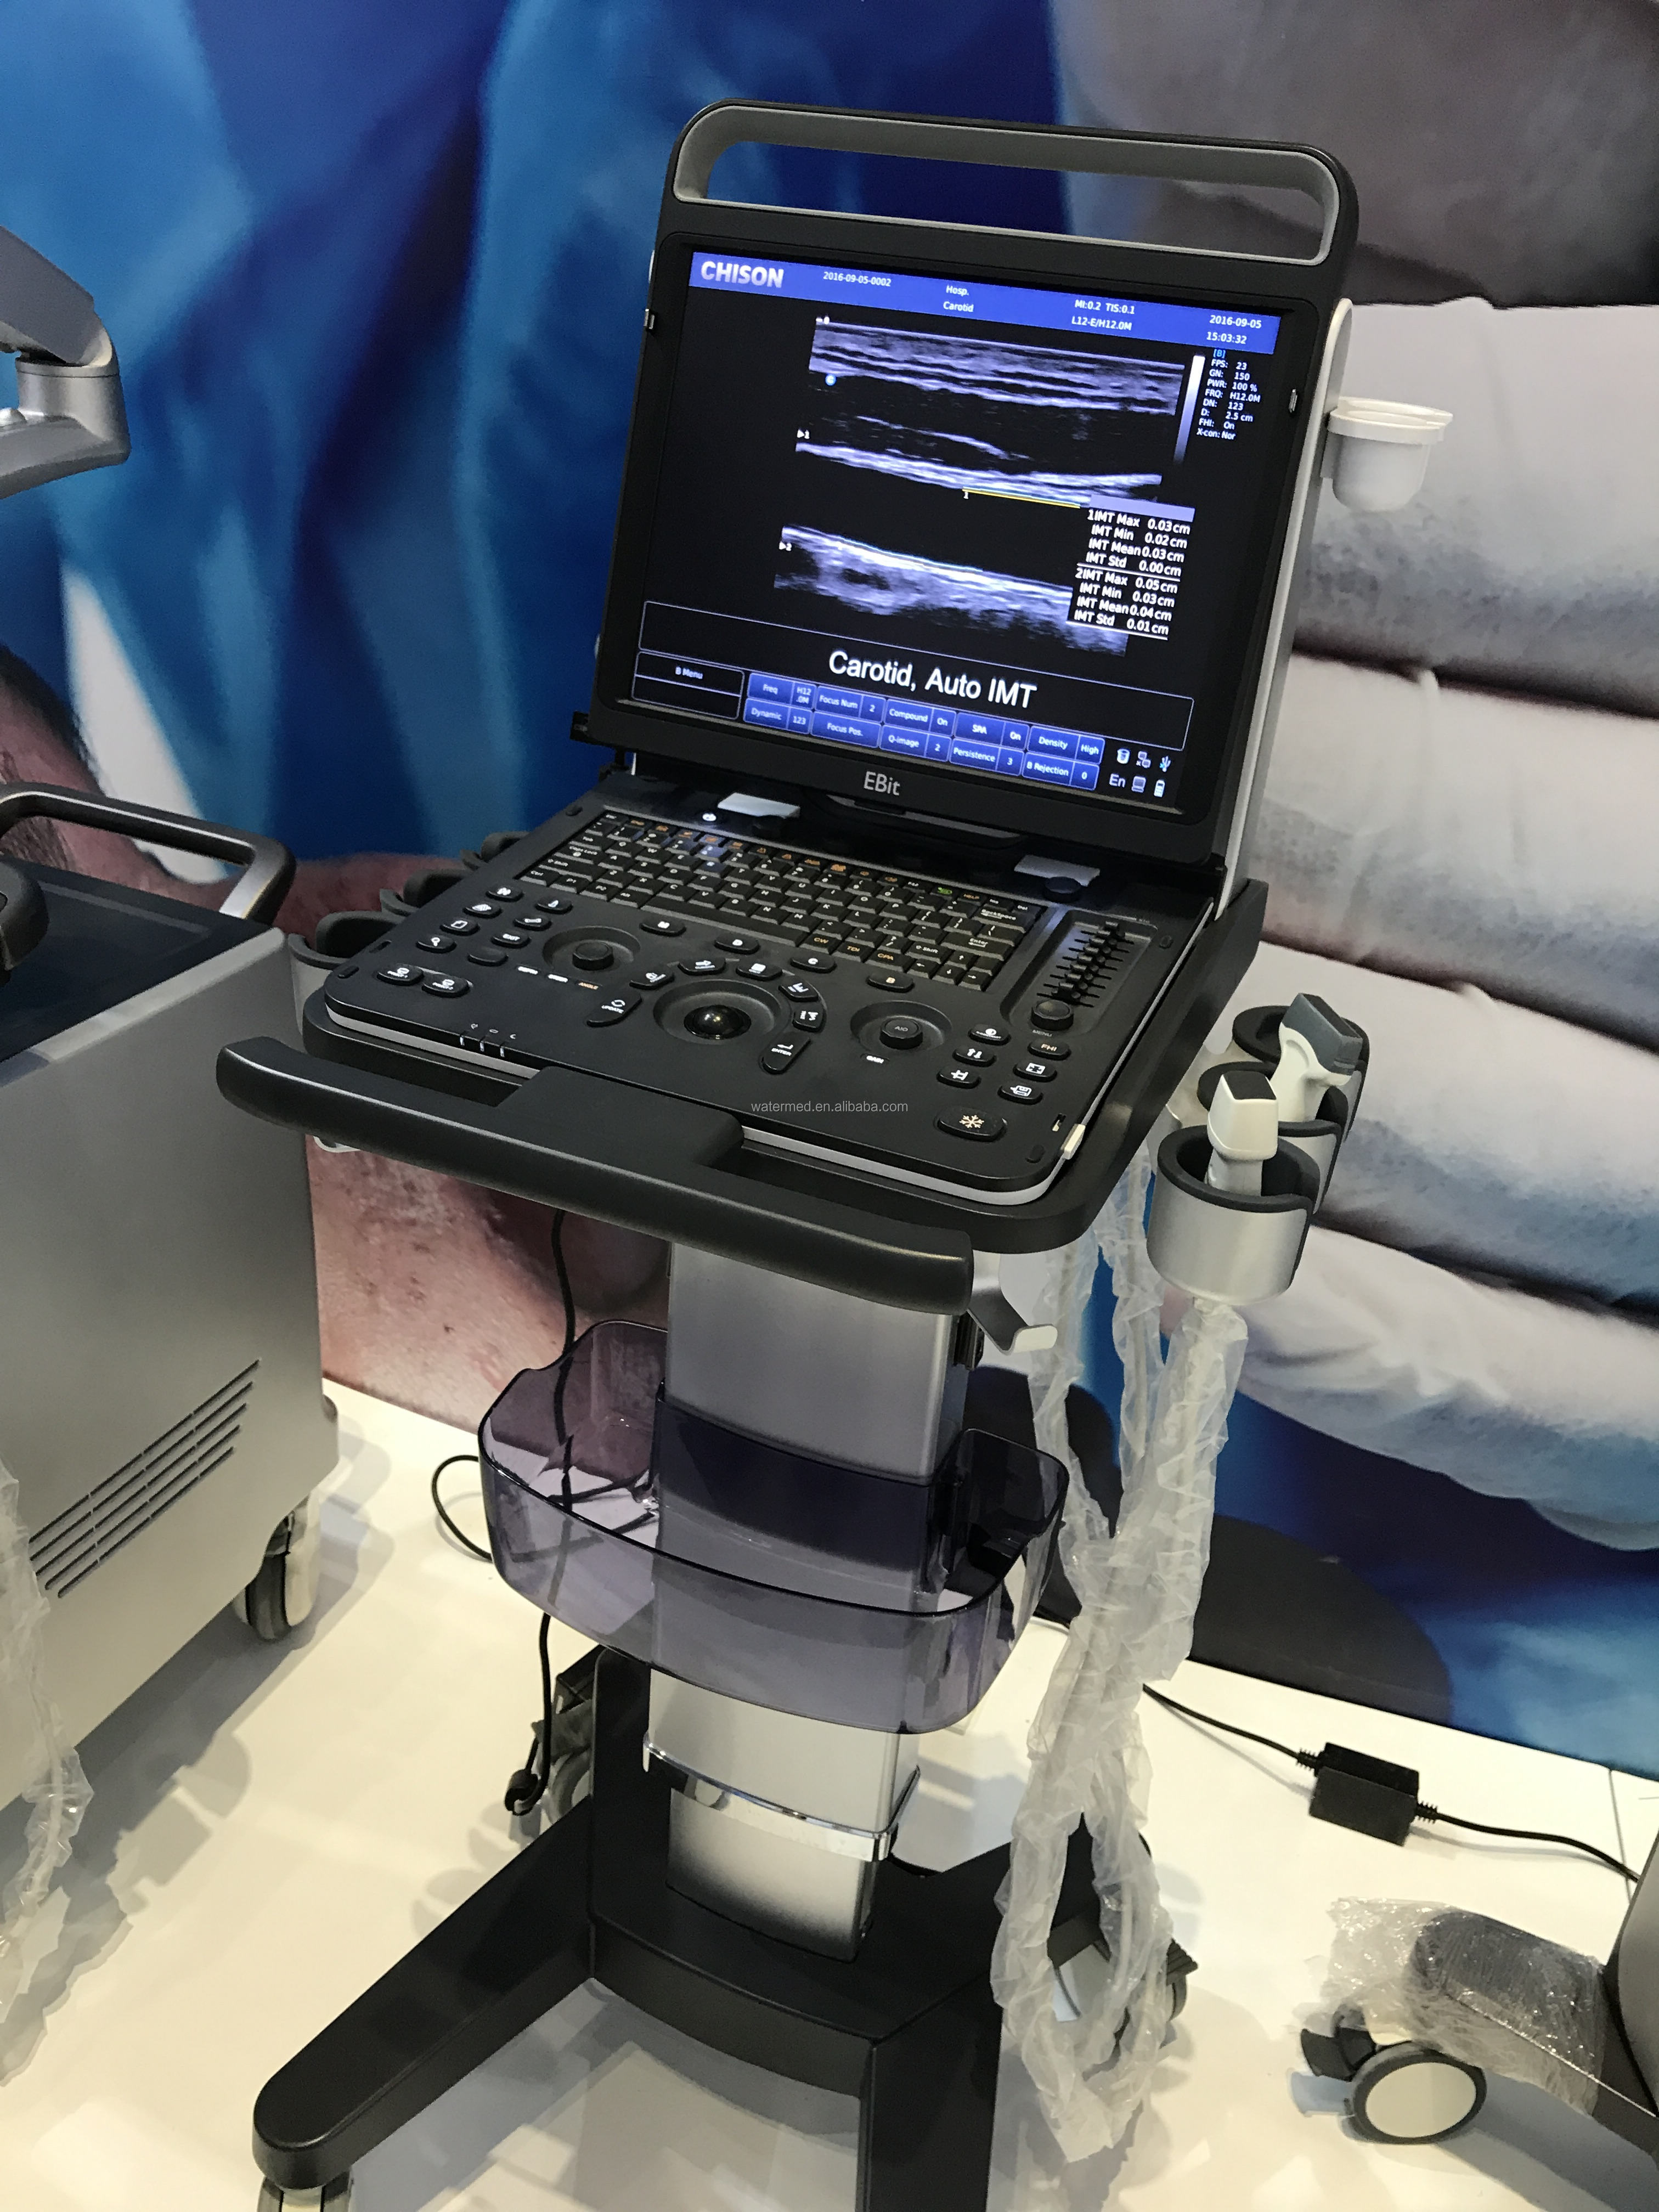

SonoScape has been in the field of ultrasound since releasing the first portable color Doppler ultrasound system. From this dedication, a large number of ultrasound technologies have emerged, especially in hand-held systems. Out of this dedication, the S9 was released as a powerful and versatile imaging platform with a futuristic design. Small in size and wide in application, the S9 is suitable for Cardiology, Radiology, Abdominal, Obstetrics, Small Parts and Urology, providing the best solution for ultrasound imaging with outstanding performance.

spatial composite imaging

Spatial compound imaging utilizes multiple lines of sight for optimal contrast resolution, speckle reduction and boundary detection, the S9 is ideal for surface and abdominal imaging for increased clarity and improved continuity of structures.

Spatial compound imaging utilizes multiple lines of sight for optimal contrast resolution, speckle reduction and boundary detection, the S9 is ideal for surface and abdominal imaging for increased clarity and improved continuity of structures.